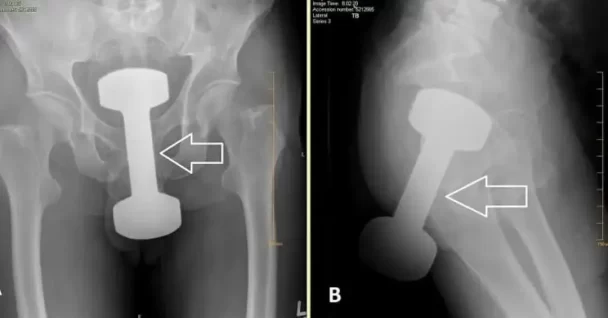

A local doctor in my country just shared this surprising post about a 2.5KG dumbbell, as the patient was unwilling to explain how the incident occurred.